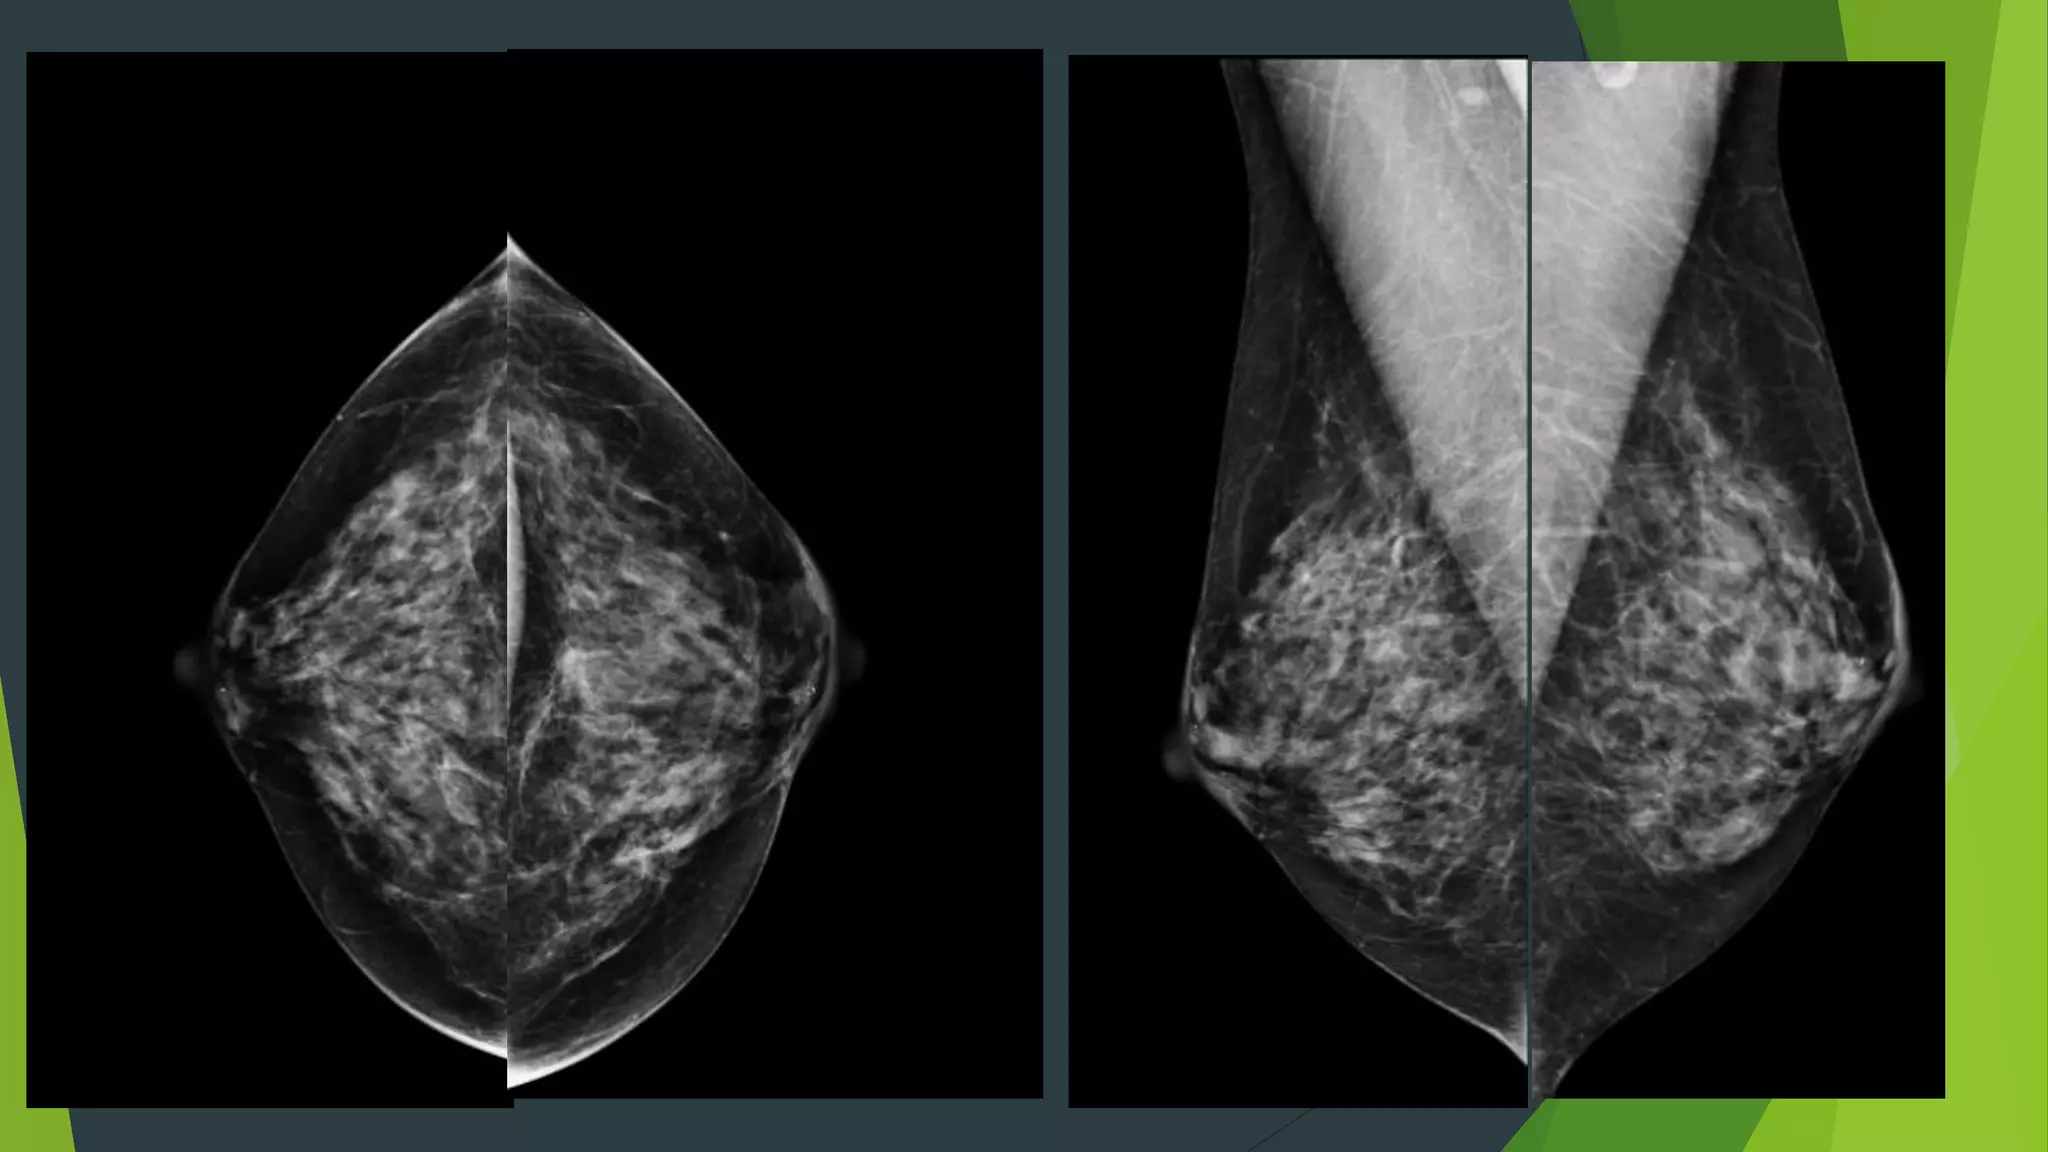

2D versus 3D Mammography

 Enhanced lesion detection – borders of lesion better defined

 Increased cancer detection rate

 Reduces false positive recalls

 Precise lesion localization

2D versus 3DMammography  Enhanced lesion detection – borders of lesion better defined  Increased cancer detection rate  Reduces false positive recalls  Precise lesion localization